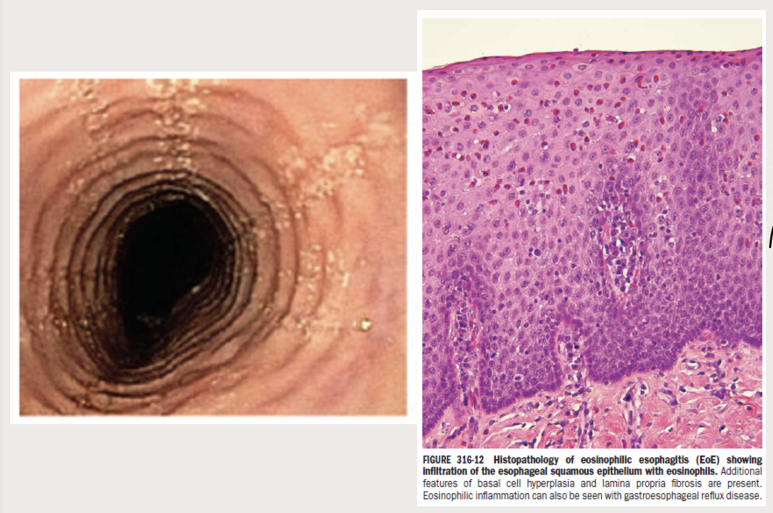

(왼쪽) 내시경소견, (오른쪽) 조직검사소견증상에서 하나씩 살펴보겠습니다.유럽 가이드라인에서는 소아와 성인의 증상을 나누어 설명을 하고 있었습니다. 소아의 경우 역류가 주된 증상으로 구토, 복통, 식사 거부 등의 증상이 있으며 성인의 경우 고형물 섭취가 어렵고 흉통이 일어나는 것으로 알려져 있습니다.

미란성 식도염의 경우 붉은 발적과 발적병변 주변에 부종 소견이 있는 반면 호산구 식도염의 경우 Furrow와 ring이 특징적인 소견입니다.

주의할 점은 내시경 소견으로 호산구 식도염을 진단해서는 안 된다는 것입니다. 예를 들면, EREFS 시스템이라는 것이 있습니다. 이 점수체계는 호산구 식도염 내시경 소견의 중증도를 점수화하여 기술하는 기준입니다. 중요한 것은 이 점수가 높다고 해서 호산구 식도염의 disease activity가 높다고 이야기하거나 관해됐다는 것을 말할 수 없다는 것입니다.

조직검사소견은 호산구가 H PF당 15개 이상 검출되는 것이 가장 중요하며, ECM 공간이 더욱 증가하고 basal zone hyperplasia가 동반되는 특징을 가지고 있습니다.